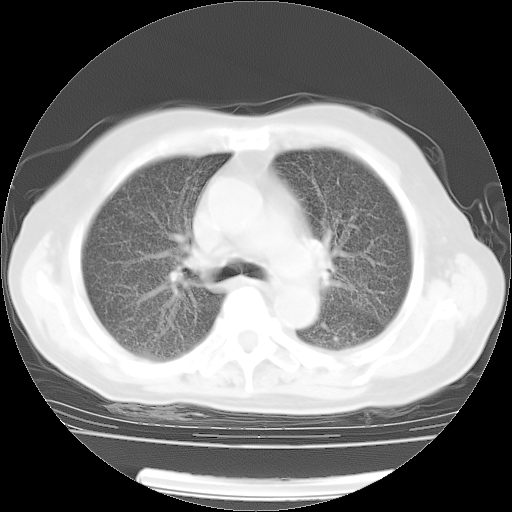

4月14日肺部CT

23.JPG

24.JPG

25.JPG

26.JPG